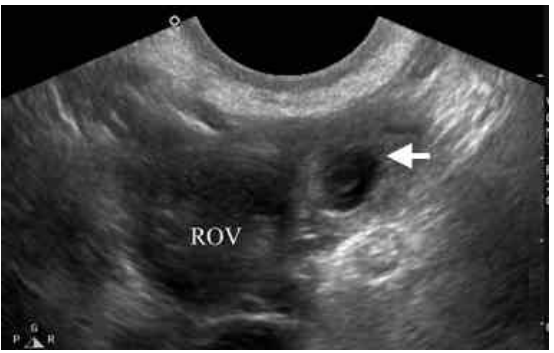

38 一位 28 歲女性已有一個半月月經沒來,近兩日常感覺右下腹疼痛,今日則因疼痛加劇而就醫,經陰 道指診發現子宮有觸壓疼痛的情形,同時子宮右邊處亦有觸壓疼痛的情形。尿液懷孕試驗呈現陽性反應,超音波掃描發現右邊卵巢(ROV)旁有囊狀腫塊,大小約 2.5×2.8 公分(箭頭所指之處), 此患者最適合之診斷為:

(A)輸卵管外孕(tubal pregnancy)(B)卵巢腫瘤(ovarian tumor)(C)輸尿管水腫(hydroureter)(D)輸卵管卵巢膿瘍(tubo-ovarian abscess)